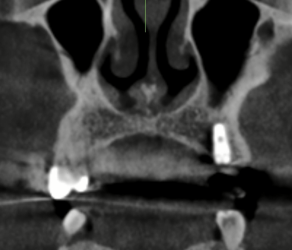

I do have more x rays that I’ll attach here.